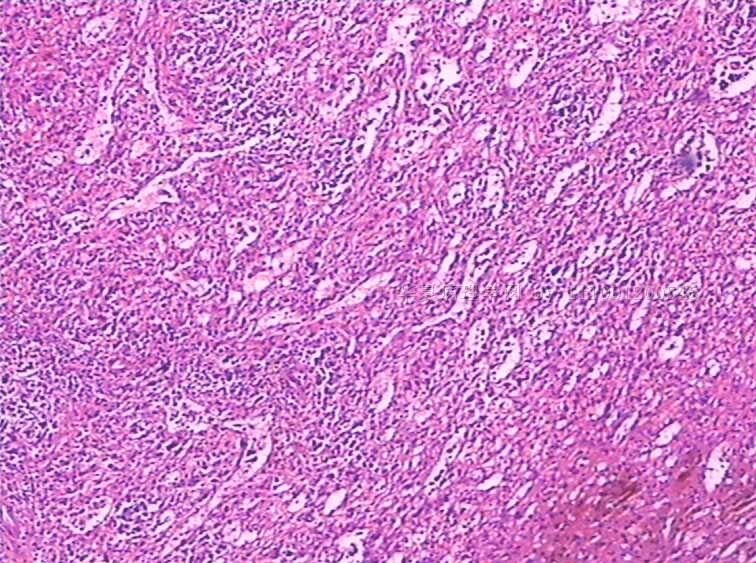

性别:

女

年龄:

49

标本名称:

反复发热,全血细胞下降1月余.CT示肝、脾肿大。骨髓检查:增生活跃,红系增高。

手术所见:脾巨大,内有梗死。肝表面光滑、肿胀。肝门淋巴结肿大,无腹水。

巨检:脾切除一个,20×15×8cm.切面灰红,有多个灰白区,最大8×6×3cm,呈楔性,小者绿豆大小

见到一些异型细胞,细胞质几乎看不到。考虑为淋巴造血系统肿瘤,脾脏原发淋巴瘤可能。

是好多组织细胞吗?期待中